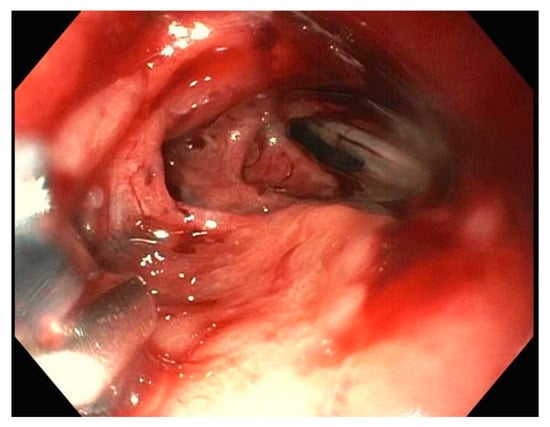

5. Stents